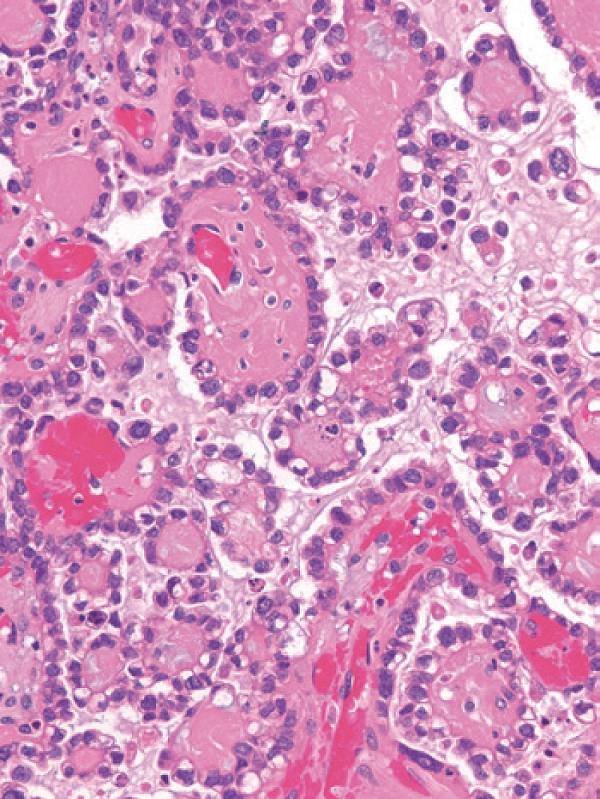

彩图4-2 卵巢透明细胞癌呈现典型管状囊性结构

彩图4-3 卵巢透明细胞癌

乳头状结构中基质玻璃样变是许多透明细胞癌乳头中的典型特征

彩图4-4 典型混合细胞类型卵巢透明细胞癌,少量管状囊性结构(右上)与大量含透明细胞质的细胞结节样生长共存(左下)